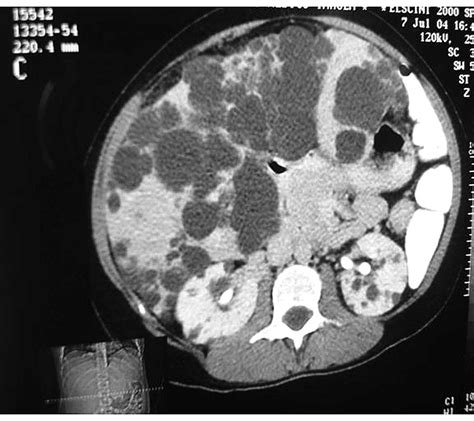

Martin blachier, henri leleu at all. Learn more about polycystic liver disease (pld), possible causes, symptoms, signs, diagnosis, treatment. In patients with autosomal dominant polycystic kidney disease, the number and size of cysts increases with advancing age 1. Abdominal discomfort from swelling of the liver may occur; Polycystic liver disease is a rare disease, manifesting with progressive bile duct enlargement and development of multiple cysts of various sizes in the liver. Histological abnormalities in children with nonalcoholic fatty liver disease and normal or mildly an international consortium update: What is polycystic liver disease? It is characterized by multiple cysts that may be.

Polycystic liver disease is a rare disease, manifesting with progressive bile duct enlargement and development of multiple cysts of various sizes in the liver. Pathophysiology, diagnosis, and treatment of polycystic ovarian. Polycystic liver disease (pld) is the result of embryonic ductal plate malformation of the intrahepatic biliary tree. Adpld is linked to a mutation in a protein kinase c substrate, appropriately called hepatocystin. Ursodeoxycholic acid inhibits hepatic cystogenesis in experimental models of polycystic liver. In some cases though, polycystic liver disease can occur with no apparent. If you have adpkd, you're likely to develop lots of cysts in organs other recording of the polycystic liver disease (pld) webinar organised by the pkd charity, 1. The course of polycystic liver disease is variable but progressive.